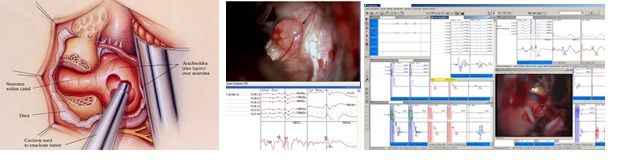

Intraoperatives multimodales Neuromonitoring

Der kombinierte Einsatz der beschriebenen Monitoring Methoden im Operationssaal soll helfen die chirurgischen Resultate zu optimieren, sowie neurologische Defizite während eines Eingriffs zu verhindern.

Die Operierenden erhalten dabei kontinuierliche Informationen über den Funktionszustand überwachter Nervenbahnen. Darüber hinaus besteht die Möglichkeit durch Mapping- und Stimulationsmethoden Informationen über die funktionelle Wertigkeit und Integrität von kritischen neurologischen Strukturen des Gehirns, des Hirnstammes oder des Rückenmarkes zu erhalten. Das gibt zusätzliche Sicherheit im Verlauf einer Operation.

Bei Operationen im Kleinhirnbrückenwinkel hat sich die Lokalisation und Überwachung des N. Facialis, als auch der kaudalen Hirnnerven durch Elektrostimulation und Ableitung von Muskelantwortpotentialen, sowie des EMG bewährt. Ebenso werden kontinuierlich Funktionen des Hörnervs sowie sensibler und motorischer Leitungsbahnen überwacht.

M.Samii/M.Tatagiba aus Strategies in Neurologic Surgery, Upjohn Company Sep.1994

Für spinale Eingriffe mit Raumforderungen, die das Rückenmark selbst betreffen, steht als Ergänzung zur Überwachung der sensiblen und motorischen Leitungsbahnen zusätzlich die Ableitung der sogenannten D-Welle über einen Katheter direkt vom Rückenmark zur Verfügung. Das ermöglicht, im Falle sich verschlechternder Ableitungen an den Zielmuskeln, weiterhin Informationen über den funktionellen Zustand des Rückenmarks zu erhalten.

Sitzt der Tumor im Bereich von Nervenwurzeln, die bereits das Rückenmark verlassen haben, besteht die Möglichkeit durch Stimulation zwischen den verschiedenen sensiblen und motorischen Nervenwurzeln zu differenzieren, wie auch Reflexe zu prüfen, um mehr Informationen über die Integrität sakraler Nervenwurzeln die zur Blasensteuerung beitragen, zu erhalten.